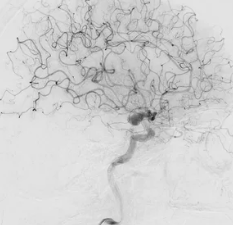

| ① CT 또는 MRI 검사 | 출혈 위치 및 범위 확인 (CT가 우선) |